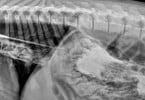

They Ate What? revela objetos bizarros engolidos por...